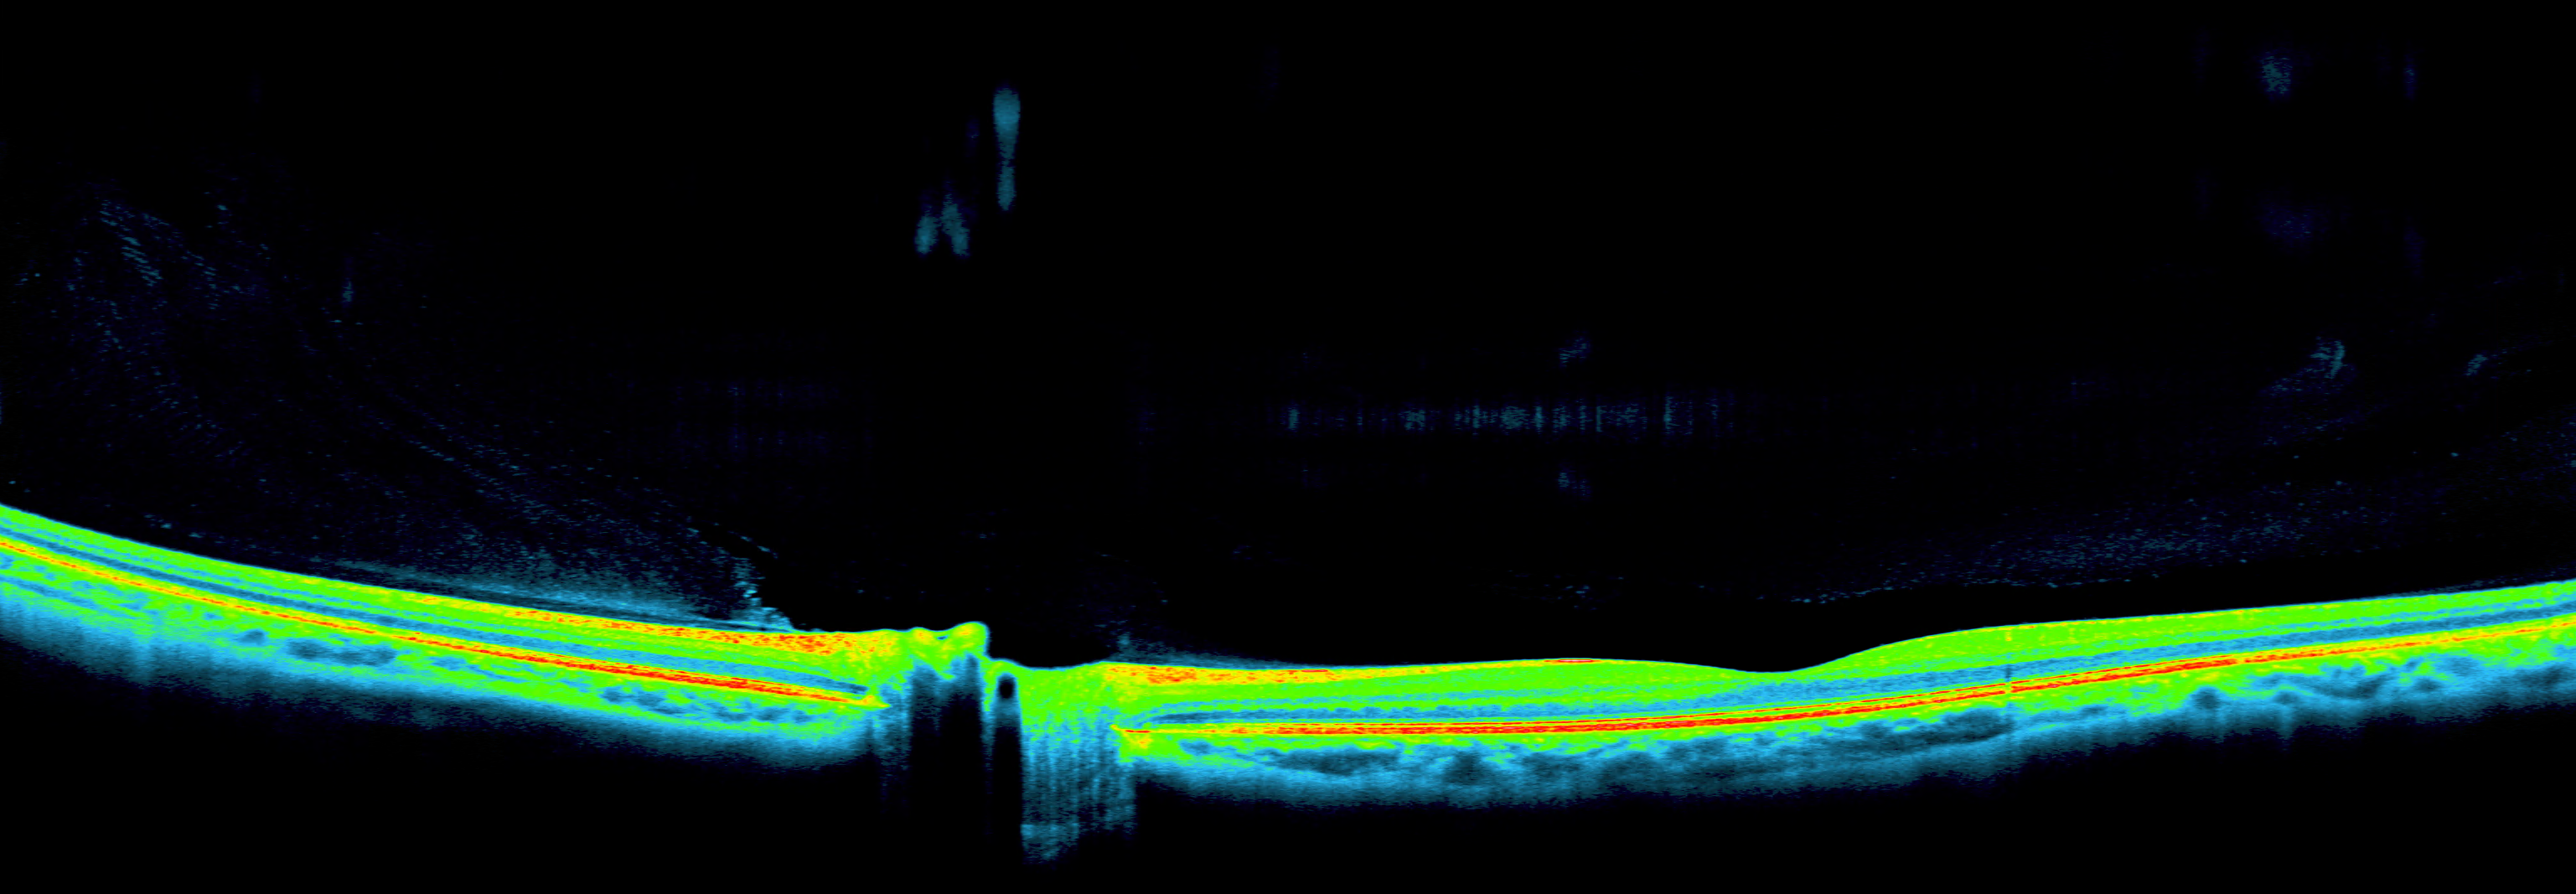

OCT Longitudinal Spine

OCT pipeline multivendor → DICOM SR

Retinal AI over Gass (OCT segmentation)

Ophthalmic DICOM viewer (React + Cornerstone3D)